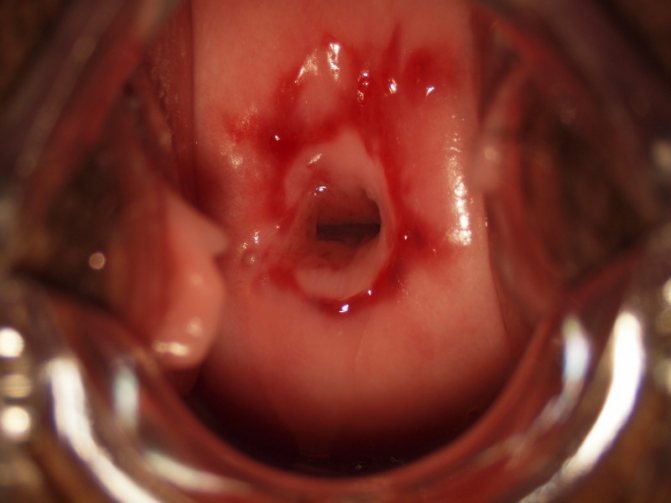

Кольпоскопия — исследование шейки матки специальным аппаратом, который увеличивает и подает на монитор изображение. Благодаря этому бесконтактному и абсолютно безболезненному способу диагностики можно увидеть атипичную поверхность слизистой оболочки.

Кольпоскопия

• Во время кольпоскопии может быть произведен простой осмотр шейки матки, а также осуществлен забор биоматериала для дальнейшего исследования

• Если при простом взятии мазка могут быть взяты клетки со здорового участка эпителия, а атипичные останутся незамеченными, то при кольпоскопии существует большая вероятность выявления пораженного участка и дальнейшего исследования его клеток

• Если при кольпоскопии были обнаружены измененные участки, то для определения тактики лечения врач может назначить биопсию. Этот метод диагностики осуществляется под местной анестезией и представляет собой забор фрагмента ткани с видоизмененного участка